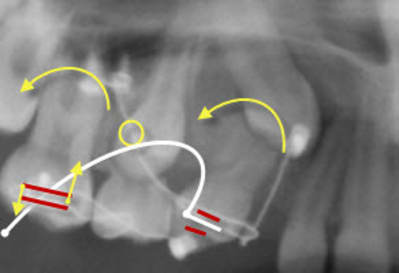

fil en titane plié à 90° collé directement sur la face vestibulaire de la prémo (comme sur le dessin) avec du composite et un simple bracket collé sur la face vestibulaire de la 6...le fil est activé simplement en l'engageant dans le bracket et verrouillé avec une ligature élastomérique par ex...

Normalement ça devrait donner un truc de se genre.

La configuration du fil va exercer une tension plus importante sur la prémolaire, le moment sera plus important sur la prémolaire que sur la molaire.

La lois d'équilibre mécanique impose donc un moment s’exerçant sur l'ensemble du System ( système composé de 16 et 14) dans le même sense de rotation que le moment le plus faible.

Donc le système va tourner dans le même sense que la 16. Donc intrusion de 16 et extrusion de 14